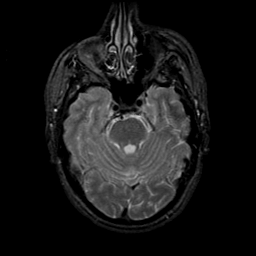

MR Study #9, April 14, 1991 -- Slice #15